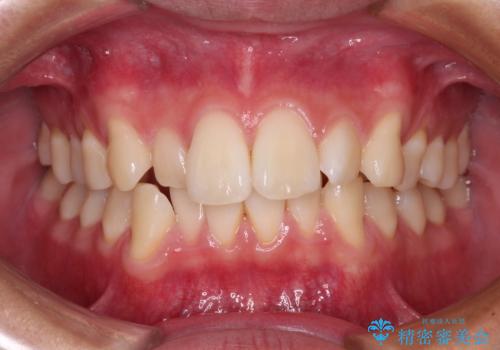

- 上下のデコボコと前歯のクロスバイトを改善したいとのことで来院された患者様です。

極力短期間で治療したいとのことで、ワイヤー装置による矯正治療を行うこととしました。

お住まいが遠方であったため、マウスピースによる矯正治療も提案しましたが、ご自身でのマウスピースの管理の面倒くささと、なるべく早く治療を終えたいとのことで、ワイヤー矯正を選択されました。